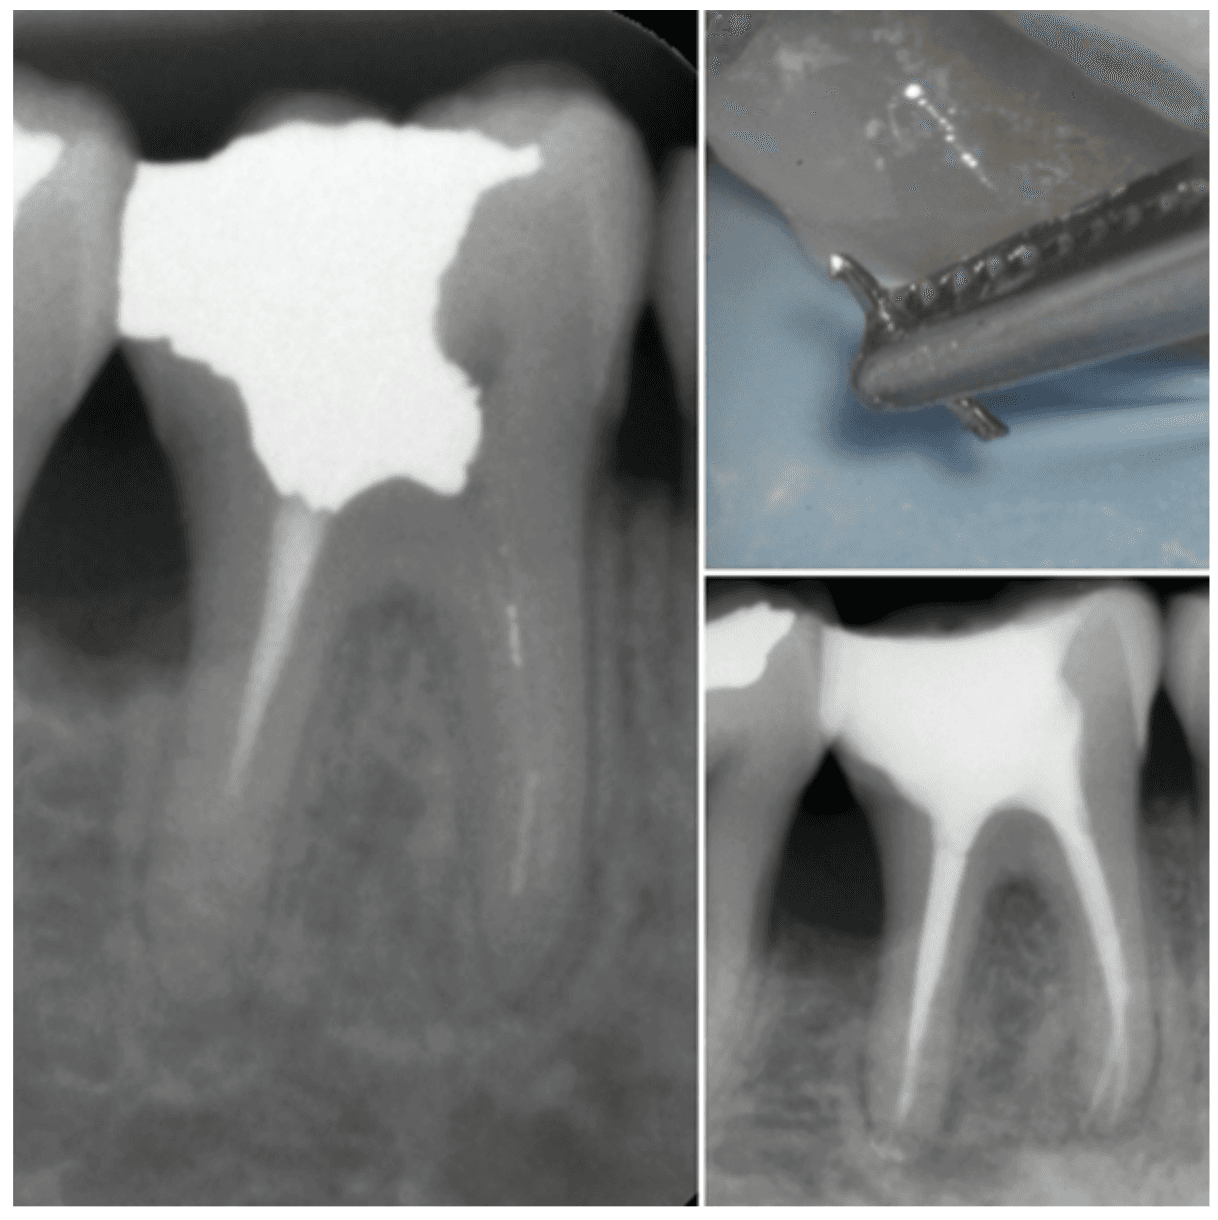

KREENA'S CASES